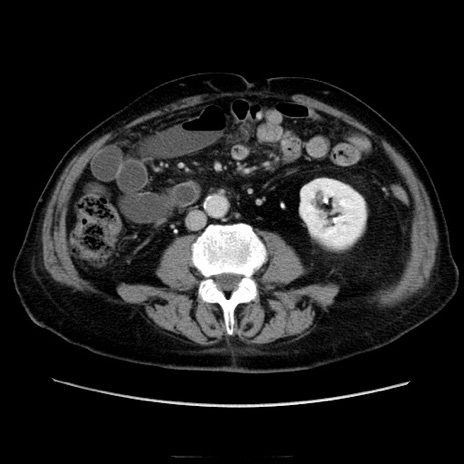

症例21(横断像)

【症例】70歳代男性

【主訴】腹痛

【現病歴】肝硬変・肝細胞癌にてかかりつけの方。約9時間前に食後より腹痛出現。症状が徐々に増悪し、嘔吐出現したため来院。

【既往歴】肝硬変、肝細胞癌(RFA、TACE後)

【身体所見】意識清明、表情苦悶様、BT 36℃、BP 129/78mmHg、P 88bpm、SpO2 97%(RA)、右上腹部から心窩部にかけて圧痛あり、反跳痛なし、筋性防御あり。

【データ】WBC 5800、CRP 0.16